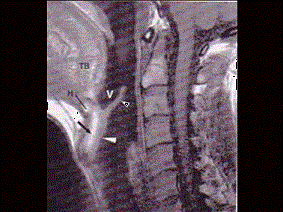

问题 男,16岁,咽异物感6年,无咽部出血及吞咽障碍。检查:舌根部中央有半球形肿物隆起,粘膜光滑,质地中等。颈部淋巴结不大: MRI检查结果如下图,下一步最重要的检查是 ( )

选项 A、针吸活检 B、纤维喉镜 C、颈部CT D、放射性I扫描 E、颈部彩超

答案 D

解析 D